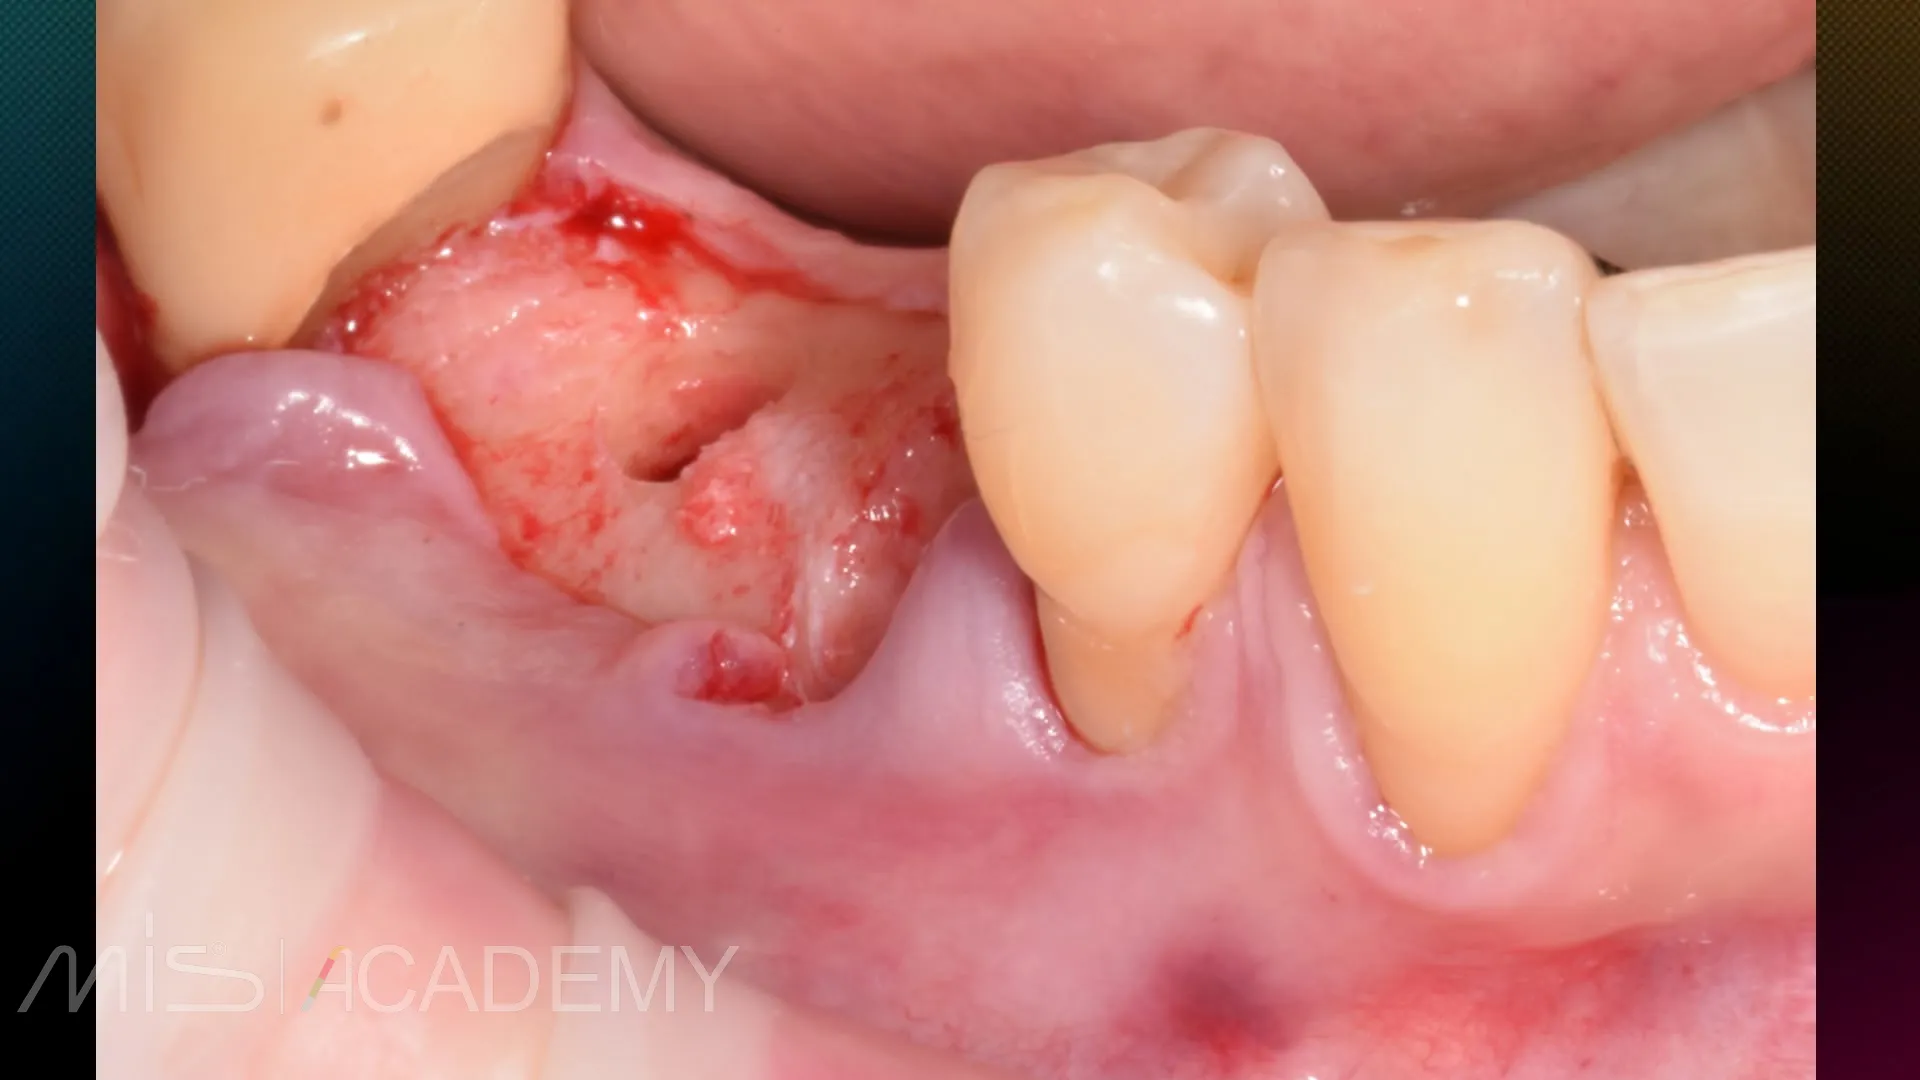

— Хирургическое закрытие рецессий на зубах 4.3, 4.4 методикой КСЛ.